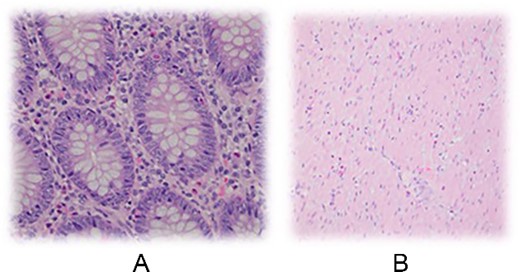

Histopathological examination is crucial in confirming the diagnosis of eosinophilic appendicitis. Characteristic findings include eosinophilic infiltration of the appendix wall, absence of granuloma formation or parasites, and exclusion of other causes of eosinophilia, such as malignancy [3, 4]. As noted in the images below, the mucosa of appendix can be seen with a mild eosinophilic infiltrate of the lamina propria and rare intraepithelial eosinophils (Fig. 2A), as well scattered eosinophils throughout the muscularis propria (Fig. 2B and C). In any event, the management of eosinophilic appendicitis involves surgical intervention with appendectomy, similar to acute appendicitis given a majority of patient’s initial presentation within the acute setting [2, 5].

Mucosa of appendix can be seen with a mild eosinophilic infiltrate of the lamina propria and rare intraepithelial eosinophils. B Scattered eosinophils throughout the muscularis propria.